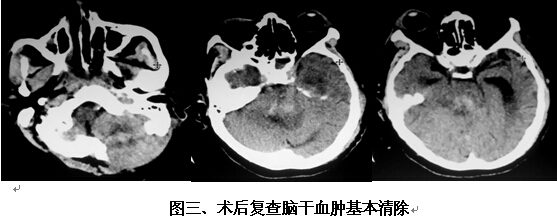

患者男,63歲,因突發(fā)神志不清2小時入院。入院時神志呈淺昏迷狀,頭顱CT提示腦干出血(橋腦、中腦區(qū)域,量約9ml)(見圖一)。神經(jīng)外科鐘三寶主任醫(yī)師查看患者后,分析患者病史、臨床表現(xiàn)及體查,結合影像學結果,考慮患者為重癥高血壓性腦干出血,需開顱行腦干血腫清除術。在發(fā)病后6小時左右,由鐘三寶主任醫(yī)師主刀,帶領李遠志副主任醫(yī)師為患者進行了手術。根據(jù)Brown兩點定位法則,采取枕下乙狀竇后入路,手術頭皮切口設計為勾型,骨窗大小約3cm*4cm(見圖二),術中清除腦干血腫約10ml,手術非常成功。術后復查頭顱CT提示腦干血腫基本清除(見圖三)。